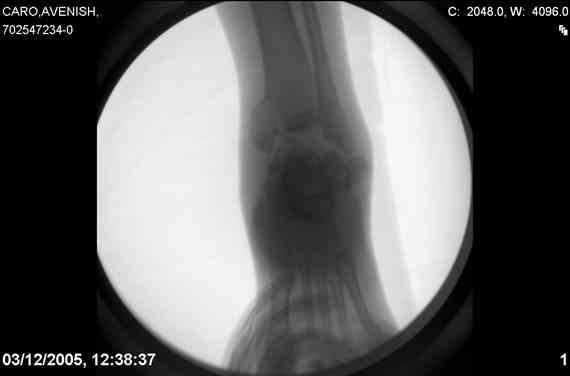

Re: Осколчатый перелом таранной кости

ya by popytalsya sobrat talus anatomichno,seichas pozdno operirovat iz za oteka,po etomy distrakziya apparatom budet optmalna.Posyalu vam podobyai moi sluchai.

14 years old girl

Fall from height ( 3rd floor)

Compressed fractures of L1-L2

Fx of orbital bone